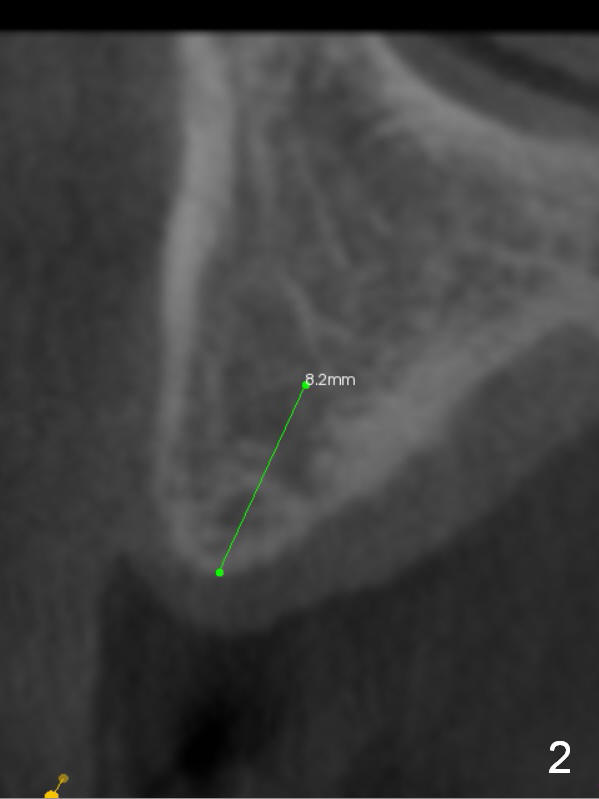

The fearful patient is satisfied with implant placement at #29 and will return to have #5 implant placed. Fig.1 is coronal section of the site of #5 (B: buccal). It shows the narrow crest and low bone density (40-200 Hounsfield unit). Start bone expansion with #15 blade slightly palatal (Fig.2 green line), followed by bone scalpels and bone blades. The latter leads to differential expansion of the buccal and palatal plates (Fig.3 arrows). Once the crestal bone is expanded, use drills or osteotomes (RTs) for deeper portion of osteotomy (Fig.4 red arrow). Finally an appropriately-sized implant is placed (Fig.5). Also prepare bone expanders. Upper Arch Reconstruction, Upper Premolar Immediate Implant Xin Wei, DDS, PhD, MS 1st edition 04/08/2016, last revision 06/12/2019